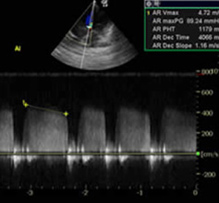

Echocardiography

Ultrasound can be used to determine the source and extent of cardiac pathology including:

• Valve structure & motion

• Chamber sizes

• Wall thicknesses

• Myocardial contractility & heart rate

• Intra-cardiac pressures and indirect systemic and pulmonary blood pressures

• Outflow tract velocities

• Congenital defects can be accurately assessed to determine treatment options and prognosis.

• Systemic blood pressure obtained on all echocardiograms with a petMAP Graphic.

• Therapeutic options are better developed as a result of knowing the extent of the pathology present.

• Response to therapy can then be measured using the animal as his own control.

• All cases are referred to a board certified cardiologist for interpretation and recommendations.